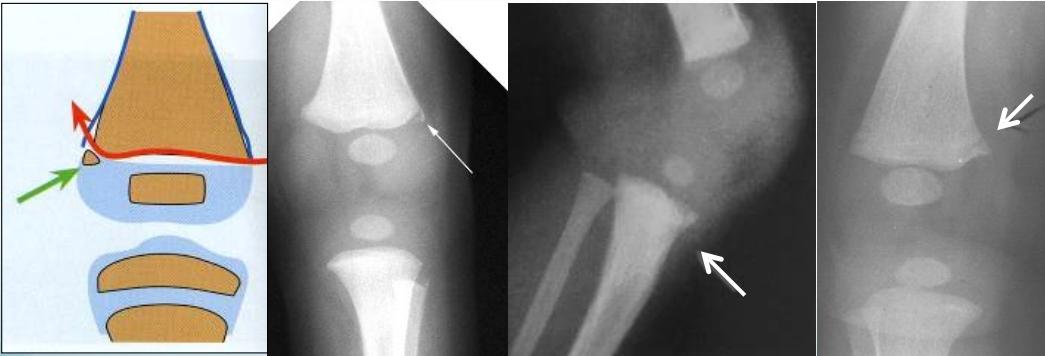

- Corner fractures (traction & rotation)

- Bucket-handle fractures (traction & rotation)

Corner Fractures:

Bucket Handle Fractures: